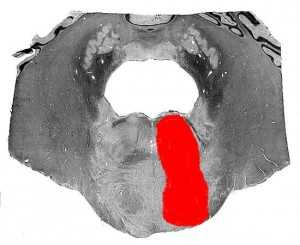

Описан французским неврологом и психиатром L. Foville в 1858 г. Патологический очаг локализуется в вентральной части моста и имеет большую протяженность в рострокаудальном направлении (по сравнению с синдромом Мийяра — Гюблера). Повреждает ядро VI нерва, корешковые волокна VII нерва, пирамидный путь. Генез синдрома Фовилля тот же, что и синдрома Мийяра — Гюблера.

Фовилля синдром

Син.: дорсокаудальный синдром покрышки моста; hemiplegia abducento-facialis alternans.

Один из понтинных альтернирующих синдромов ствола мозга. Возникает при поражении корешков и ядер VI и VII краниальных нервов, заднего продольного пучка и пирамидных путей, иногда - с вовлечением медиальной петли. Очаг при этом располагается в нижнем отделе моста по всей сагиттальной оси.

Синдром Фовилля

Синдром Фовилля является альтернирующим синдромом (сочетание поражения ЧМН на стороне патологического процесса с чувствительным расстройством на другой стороне) развивающийся при очаговом поражении нижней части моста мозга. В клиническую картину. Тем самым, вовлекаются ядра и корешки лицевого. Отводящего нервов, пирамидный путь, а также (не всегда) медиальная петли.

На стороне патологического процесса развивается периферический парез/паралич мимической мускулатуры, а также прямой наружной мышцы глаза, на противоположной развивается гемипарез/гемиплегия центрального характера, иногда в сочетании с нарушением чувствительности (болевой и температурной) по гемитипу. Описан синдром был в 1858 году неврологом A. Foville (1799-1879 годы жизни, страна проживания - Франция).